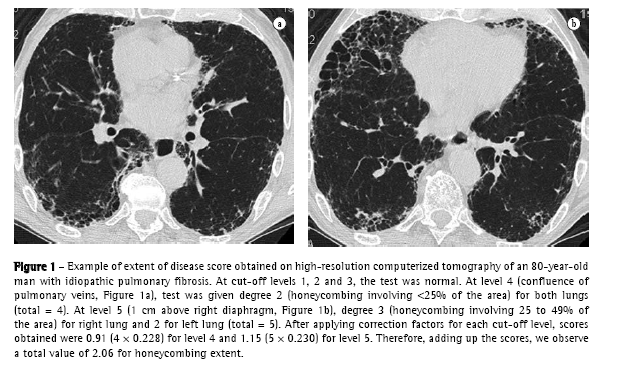

In the end, TID, reticular abnormality/honeycombing and ground-glass opacity levels were obtained by totaling the scores for each level. An example of how these scores were obtained is shown in Figure 1.

c) the following technique was used for HRCT: GE equipment, HISPEED model; 1-mm thick slices, at 1.5 s intervals and increased by 10 mm; image reconstruction with a 512 × 512 pixel matrix, using a high resolution algorithm; 1000 HU width window; −700 HU medium window level. Interpretation of tomographic findings was performed according to a consensus among four radiologists with extensive experience in interstitial disease. In the absence of histologic material, the diagnosis of IPF by HRCT was accepted only upon concordance of all readers and if all clinical and functional criteria described above were met. An initial overall analysis of the HRCT (without considering cut-off levels) was conducted, in search of the following findings: nodules, ground-glass opacities, reticular abnormality, honeycombing (cysts  3 mm and  3 mm), traction bronchiectasis, air trapping areas and emphysema.(18,19) Subsequently, the HRCT was evaluated as to the extent and intensity of interstitial lung involvement, considering five cut-off levels: 1) origin of major vessels; 2) aortic arch level; 3) carina; 4) confluence of pulmonary veins; and 5) 1 cm above the right diaphragm.(6,19-21) Using a semiquantitative evaluation system, each of these levels (right and left, separately, totaling 10 levels) was analyzed as to the following aspects:

For the analysis of HRCT findings, estimated pulmonary involvement was obtained using an influence factor ('weight') to correct different pulmonary volumes at each level, as follows(19):

origin of major vessels - weight = 0.129;

aortic arch level - weight = 0.190;

carina - weight = 0.222;

confluence of pulmonary veins - weight = 0.228; and

1 cm above the right diaphragm weight = 0.230.